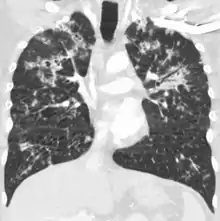

A case of miliary tuberculosis in an 82-year-old woman:

CT, 16 days after onset, showing extensive pulmonary parenchymal involvement consisting of irregular septal thickenings with ground-glass areas and centrilobular nodules with a peri-lymphatic distribution